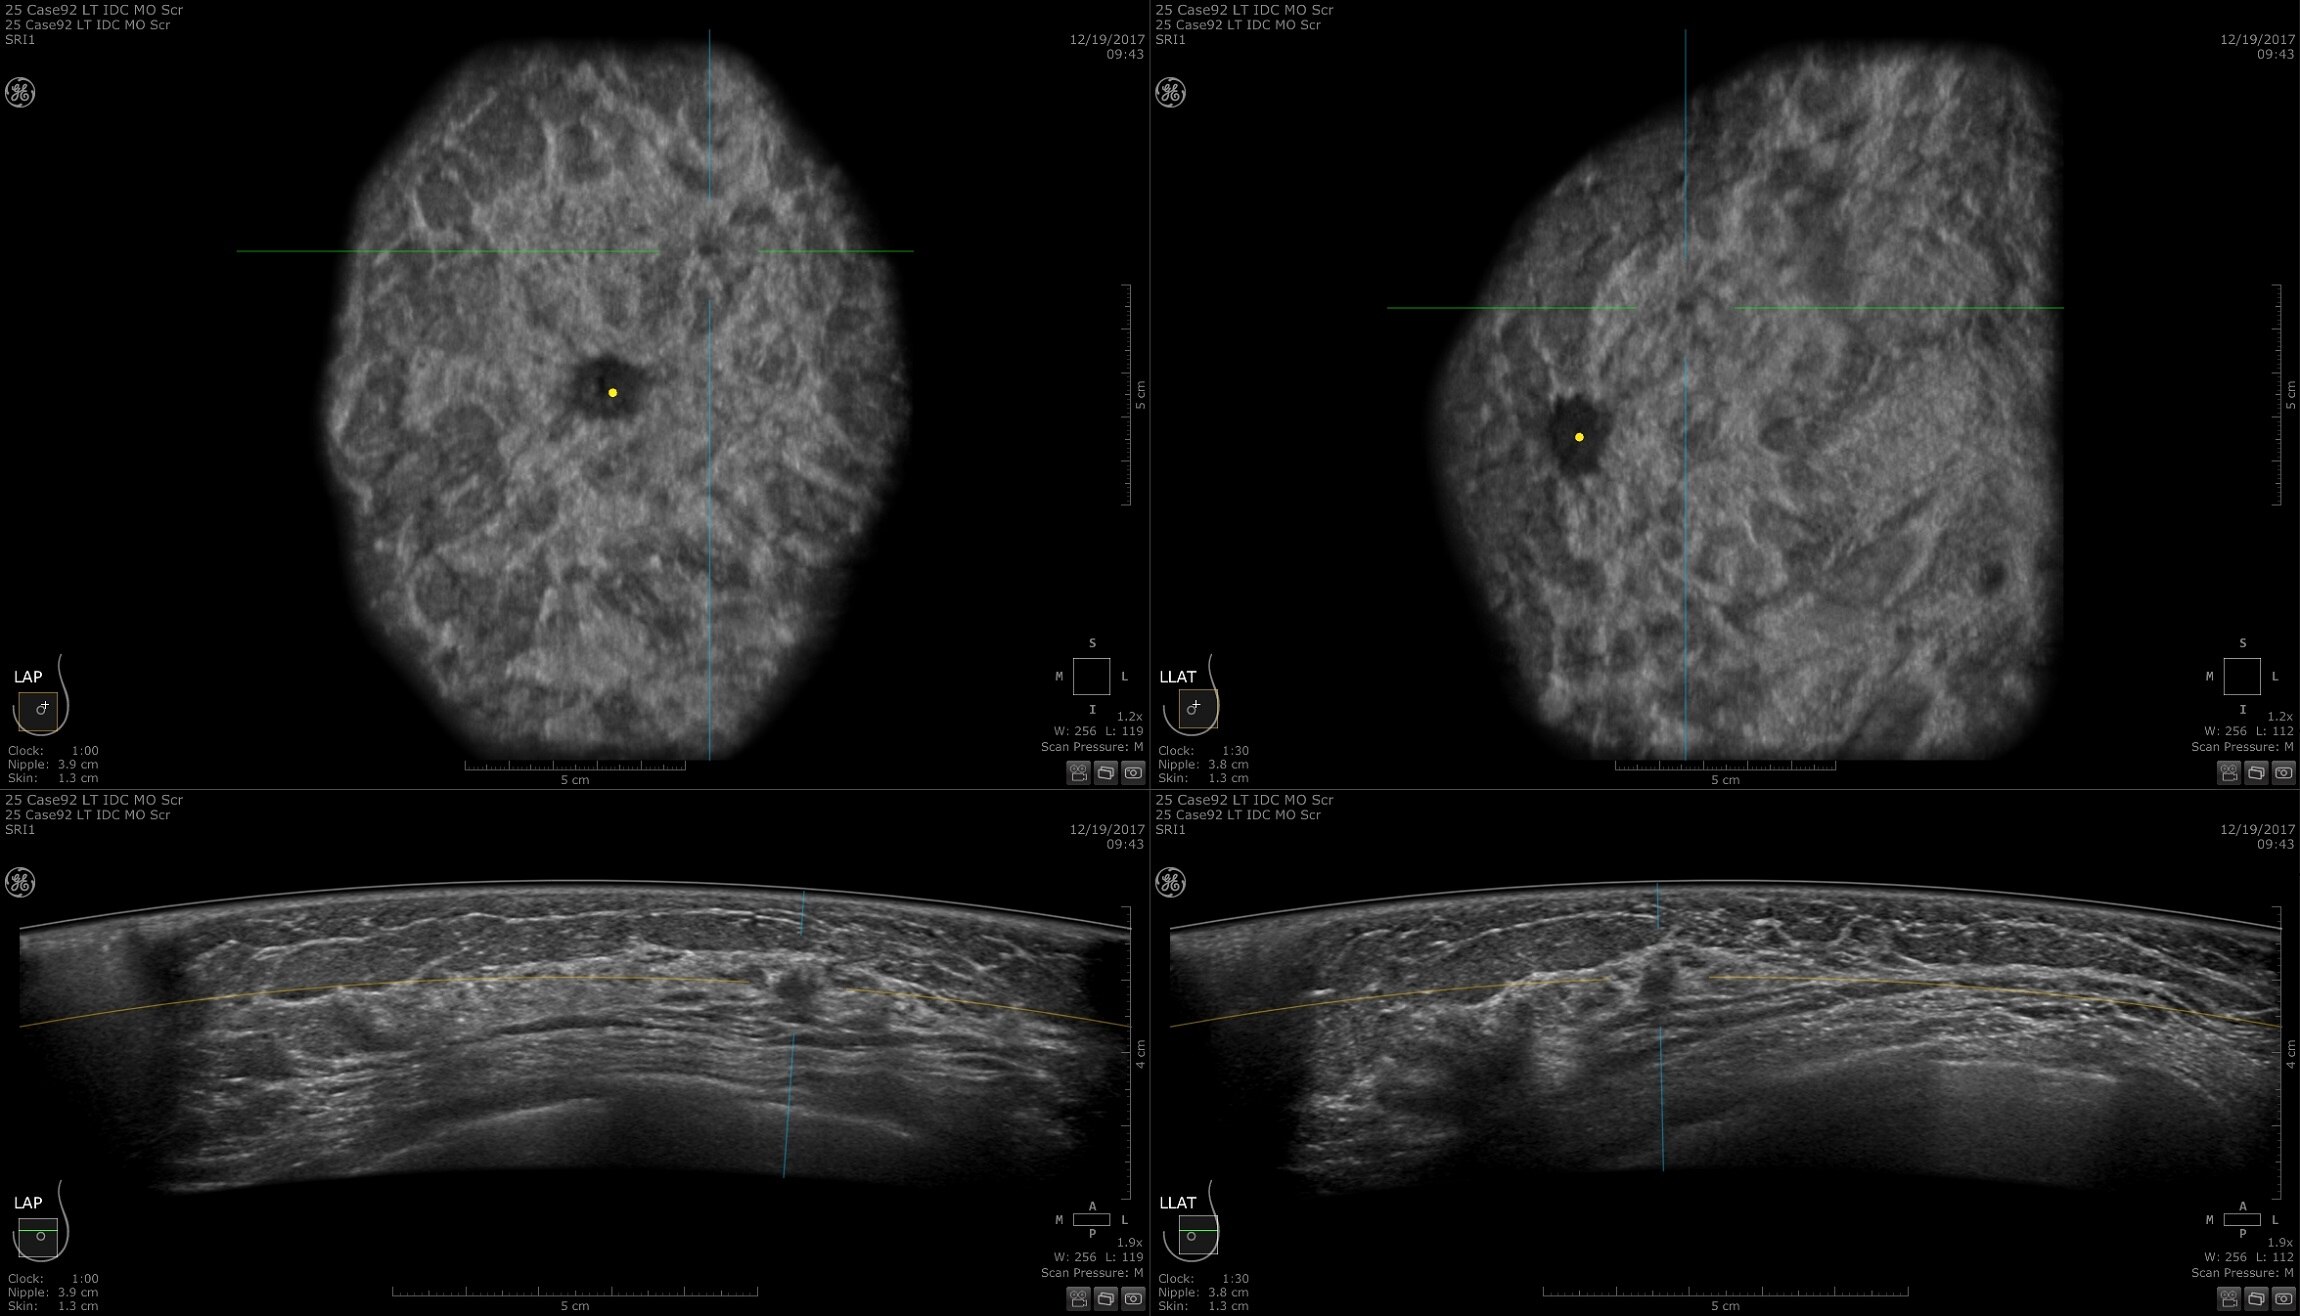

COMODIDAD EQUIPARABLE A LA DE AIR™

Simplemente una experiencia de PET/RM mejor

Las bobinas AIR™ están diseñadas para adaptarse al cuerpo humano como una manta fina. Su diseño permite reducir los artefactos de atenuación de las exploraciones de PET y mejorar la cuantificación. Las bobinas AIR™ también proporcionan una configuración más rápida, lo que permite aumentar el flujo de trabajo y reducir la exposición del técnico a los pacientes a los que se les inyectan isótopos radiactivos.

AIR x™ y AIR Touch™ son aplicaciones de flujo de trabajo inteligentes que ayudan a los técnicos a configurar y realizar exámenes con facilidad. AIR x™ detecta automáticamente la anatomía y prescribe cortes de RM, lo que permite tiempos de configuración 5 veces más rápidos y 4 veces menos clics del ratón. AIR Touch™ ajusta el promedio de la bobina para los parámetros anatómicos y del protocolo con un solo toque, y proporciona un aumento de la productividad del 59 %‡ desde la planificación hasta la exploración.

Bobinas AIR™

Nada se acerca más que AIR™. Su diseño flexible acerca los elementos a la zona de interés, lo que mejora enormemente la calidad de la imagen y la comodidad del paciente.

AIR Touch™

AIR Touch™ es una solución de flujo de trabajo inteligente que selecciona automáticamente las mejores combinaciones de elementos de bobina de RM para cada paciente en la región de interés específica.